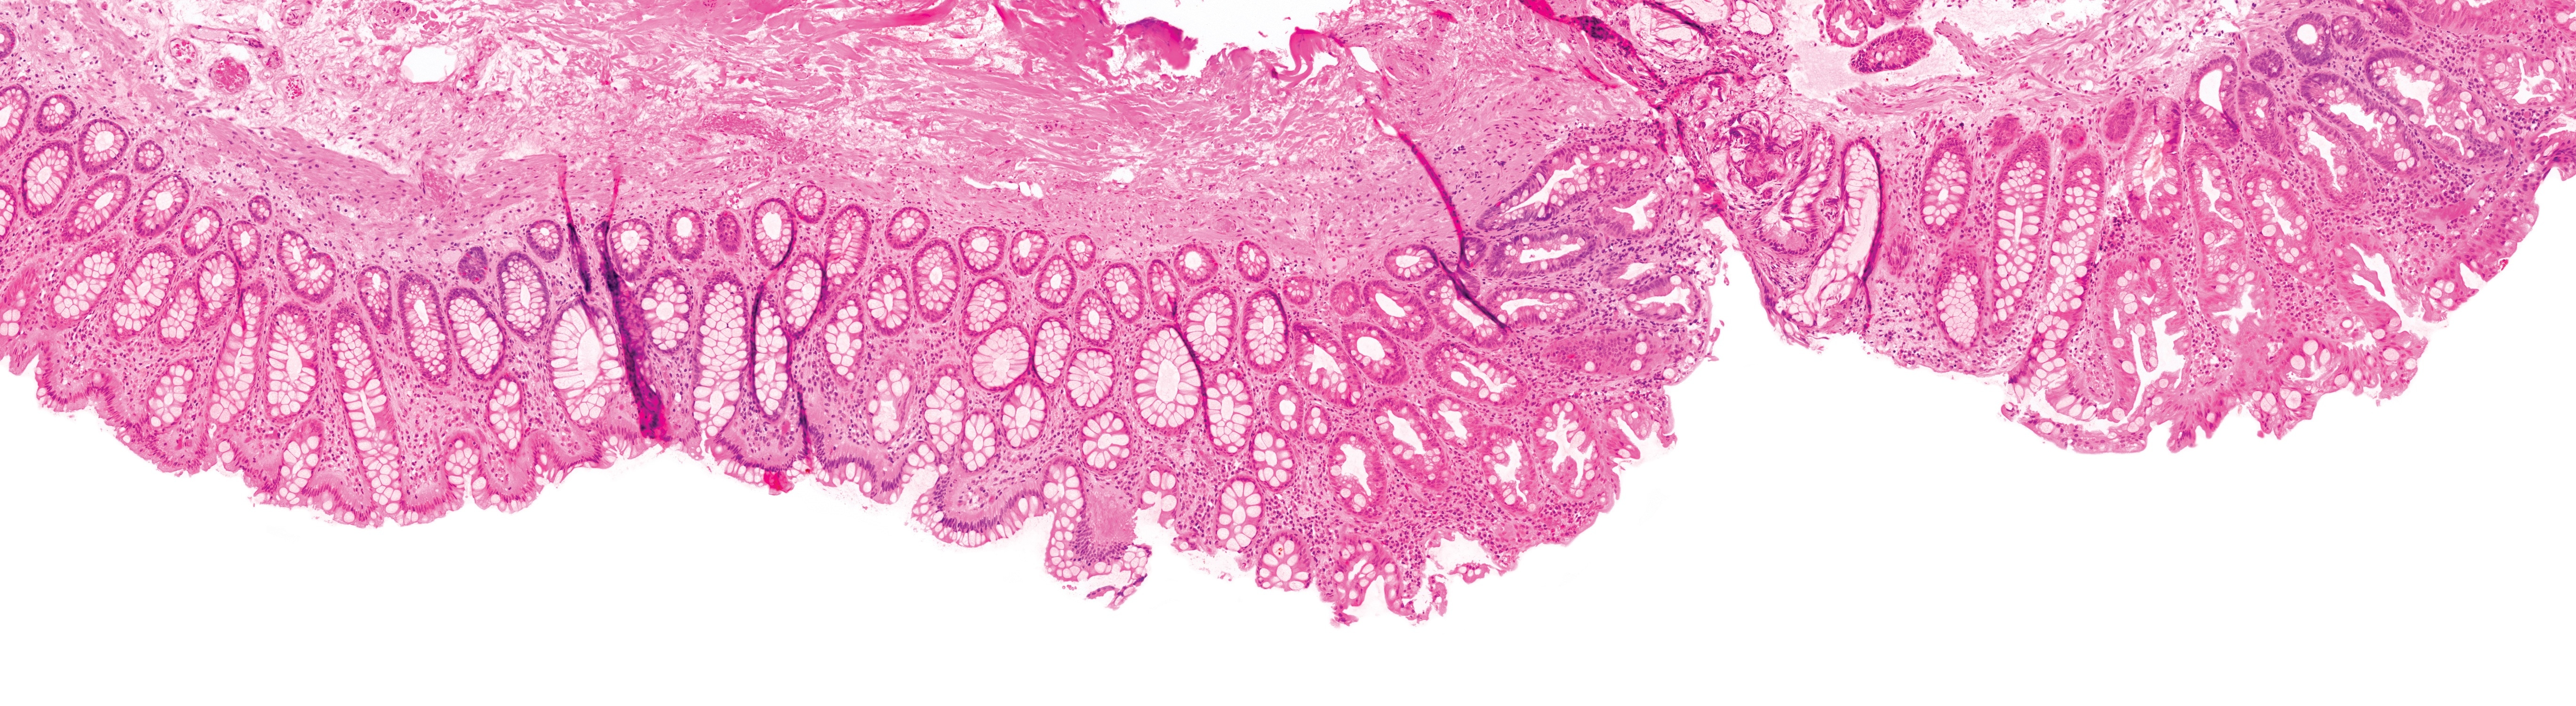

Huron Scan Index Search

Scan, index, search pathology

Image credit: Huron Digital Pathology.

One of the most exciting developments is a partnership with Huron Digital Pathology and Dell Technologies to bring intelligence to the unstructured data through image search – connecting pathologists to the vast knowledge contained in pathology reports on a real-time basis.